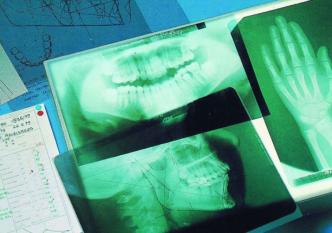

Übersichts-Röntgenaufnahme

Einzelzahn-Aufnahmen

Fernröntgen-Seitenaufnahme (FRS)

Fernröntgen-Frontalaufnahme (FRF)

Röntgenaufnahme der Hand

Um den Zustand der Zähne oder Zahnkeime festzustellen, sind Röntgenaufnahmen bei allen kieferorthopädischen Behandlungen zwingend erforderlich.